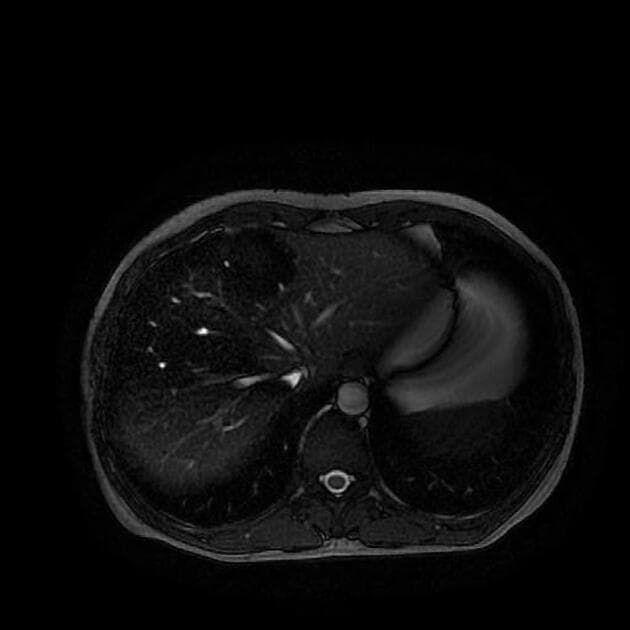

Axial C+ portal venous phase

Thiếu máu cục bộ vùng ranh giới ruột già

Có một đoạn dài thành ruột đại tràng ngang và đại tràng xuống dày thành vòng quanh (circumferential wall thickening) kèm theo hình ảnh dải mờ ở mô mỡ quanh đại tràng (pericolic fat stranding).

Động mạch chủ (aorta) có vôi hóa vừa phải và có khả năng bị hẹp độ cao (high grade stenosis) tại vị trí xuất phát của động mạch mạc treo ruột dưới (inferior mesenteric artery).

Đoạn dài dày thành đại tràng ngang và đại tràng xuống kèm theo hình ảnh viêm quanh ruột (pericolic inflammatory stranding) phân bố điển hình cho tình trạng thiếu máu cục bộ vùng ranh giới (watershed ischemia), đặc biệt khi có khả năng hẹp độ cao tại vị trí xuất phát của động mạch mạc treo ruột dưới (inferior mesenteric artery).

- Ở bệnh nhân cao tuổi có bệnh lý mạch máu (elderly vasculopath), viêm đại tràng (colitis) phân bố như vậy là điển hình cho thiếu máu cục bộ tại vùng ranh giới giữa động mạch mạc treo ruột trên và động mạch mạc treo ruột dưới (SMA/IMA watershed territory).

Thiếu máu cục bộ vùng ranh giới ruột già (Large bowel watershed ischemia)